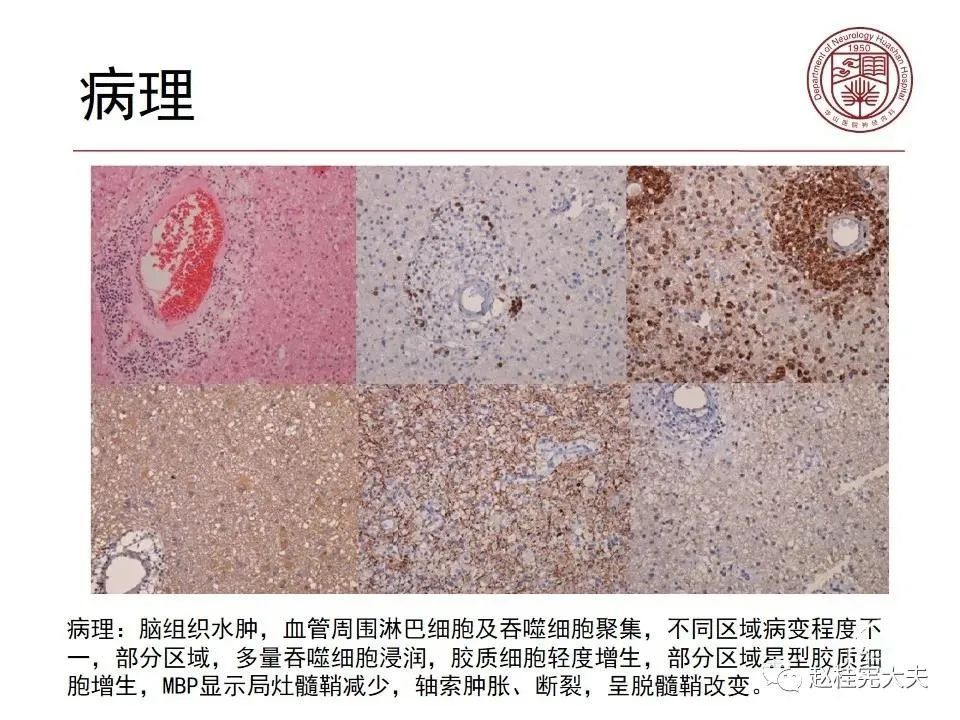

患者女性,19岁,反复头痛数年,近期加重伴记忆力下降,反复查磁共振报正常。结合病史,仔细阅片发现大脑皮层Flair、DWI异常信号。抽血查血清MOG抗体1:32,诊断MOG皮层脑炎。

在2017年2月,我曾在我的公众号就MOG皮层脑炎做过科普。(CNS免疫病文献复习系列之二:MOG抗体阳性的单侧皮质脑炎)。MOG抗体阳性的皮层脑炎,中位数年龄是37岁(27-39岁),主要的症状是癫痫发作,伴或不伴异常行为或意识障碍。所有的患者颅脑磁共振表现为Flair上偏侧皮层高信号,肿胀,SPECT提示灌注增高。脑脊液中可见中等程度白细胞增多,蛋白轻度增高。但MBP未见增高。脑炎相关的自身免疫抗体如AQP4-IgG,NMDA受体抗体、VGKC抗体均阴性。所有患者均接受抗癫痫药物治疗,在大剂量激素冲击治疗后均完全恢复,磁共振上偏侧皮层病灶消失。没有患者复发。结论:MOG皮层脑炎可能为自身免疫性,总体激素反应良好,但其表现和MOG抗体介导的中枢神经系统脱髓鞘、Rasmussen脑炎和其它已知免疫介导的脑炎均不同。